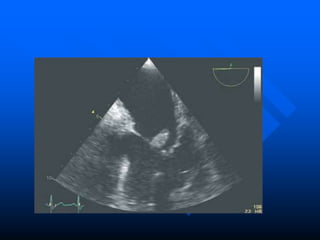

 Trans Thoracic Echocardiograpy (TTE)

– rapid, non-invasive – excellent specificity (98%) but

poor sensitivity

– obesity, chronic obstructive pulmonary disease and

chest wall deformities

 Transesophageal Echo (TOE)

– more invasive, sensitivity up to 95%, useful for

prosthetic valves and to evaluate myocardial

invasion

– Negative predictive valve of 92%